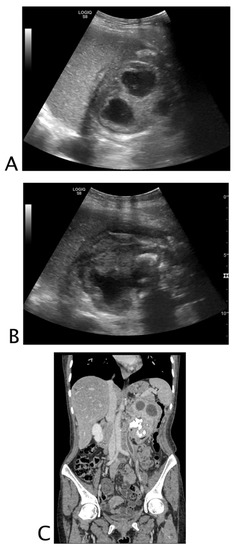

2.2.2. Urinary Tract

2.3.2. Urinary Tract